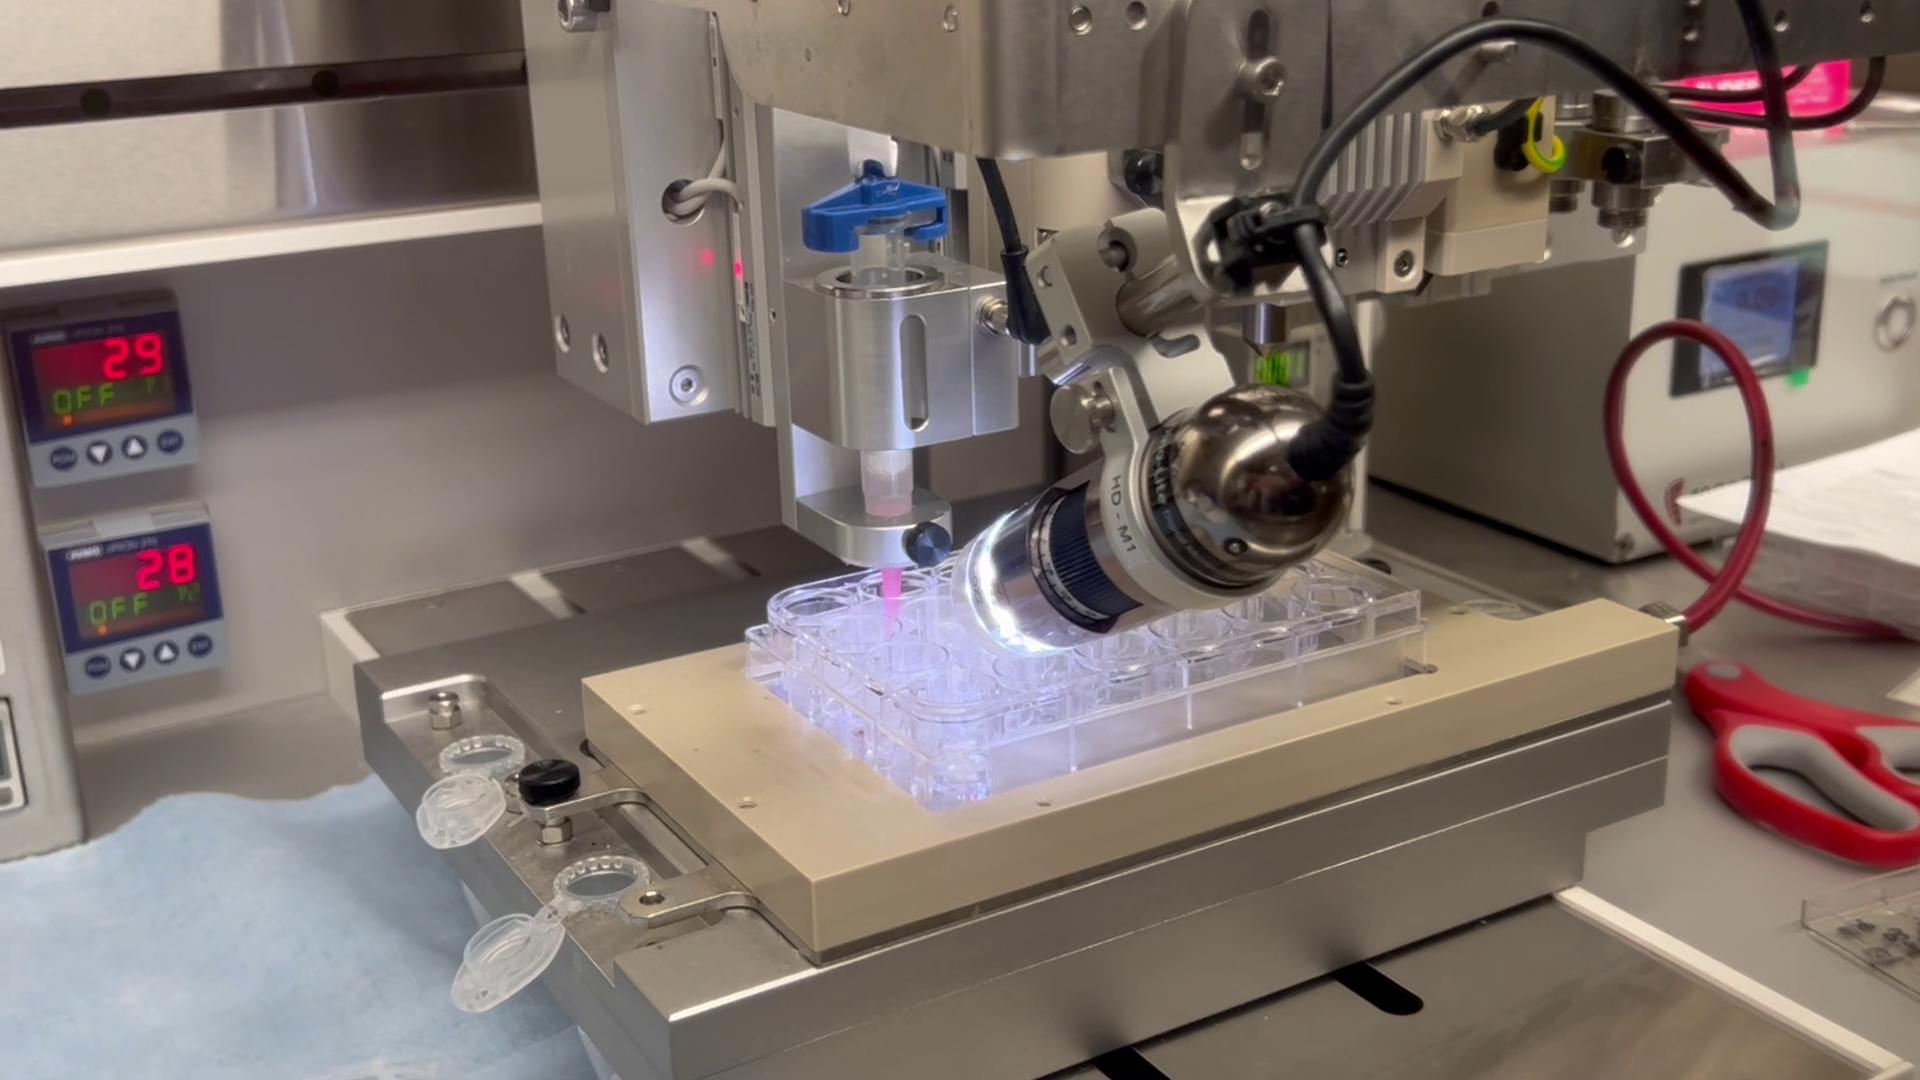

Z24 Bio develops an AI-integrated, 3D-bioprinted human-tissue platform enabling pharmaceuticals to predict toxicity earlier, de-risk pipelines, cut costs and time, reduce animal use, and avoid late-stage attrition.

We create high-fidelity human tissues by integrating 3D bioprinting, organ-on-chip microfluidics, advanced biomaterials, AI-driven analytics and modeling. This enables us to predict drug safety and efficacy with unmatched accuracy, reducing time, cost, and reliance on animal testing.

We deliver next-generation drug discovery services that replace outdated animal models with scalable, ethical, and predictive human tissue platforms. We integrate 3D bioprinting, organ-on-chip systems, AI analytics, and quantum modeling to help pharma de-risk pipelines and accelerate approvals.

Miniaturized human liver, heart, and other organ models for high-throughput screening.